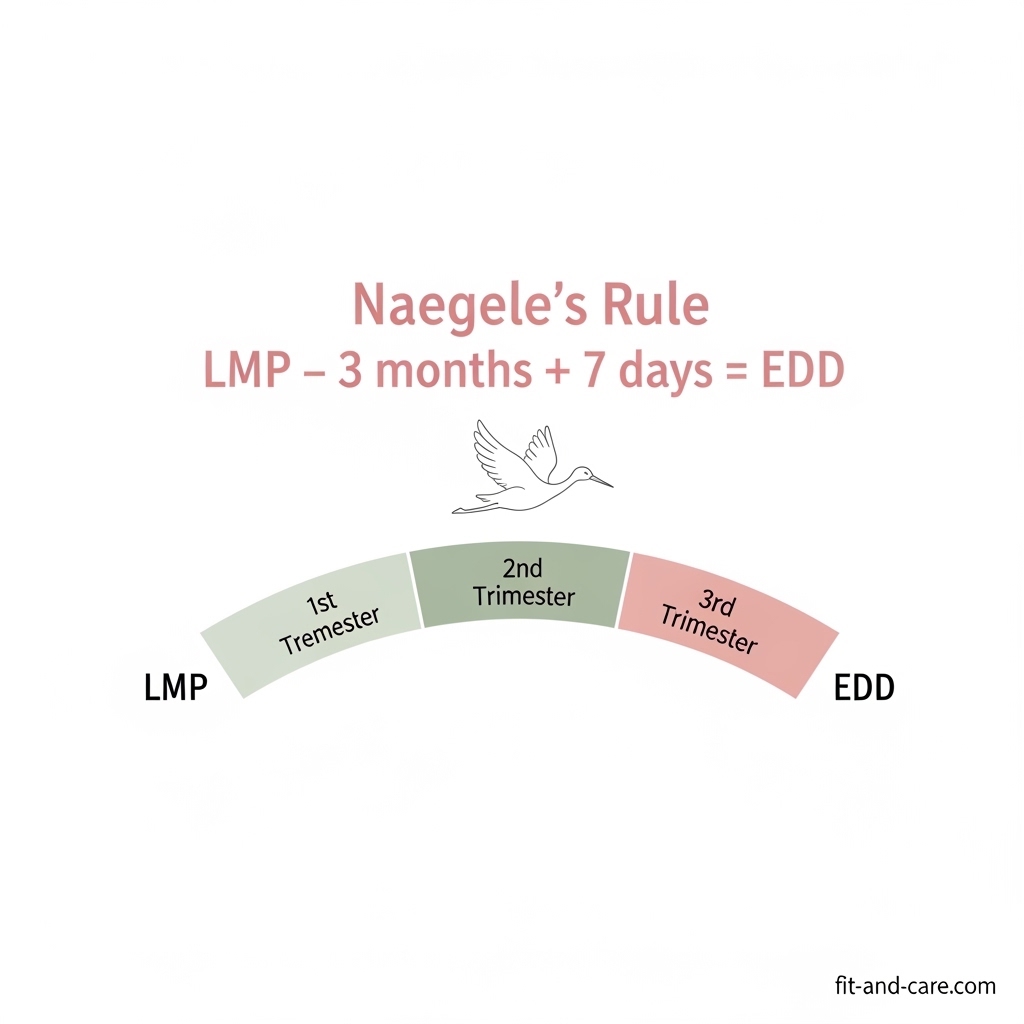

A pregnancy calculator determines your Estimated Due Date (EDD) using your reproductive data, usually on the first day of the Last Menstrual Period (LMP). The most common method is known as Naegele’s Rule; it was invented in the early 19th century by German obstetrician Franz Karl Naegele and has been used by OB/GYNs all over the world.

Naegele’s Rule: The Formula Behind Every Due Date

The formula is simple: take the first day of your last menstrual period, add 280 days (40 weeks), then subtract 3 months and add 7 days. Written out:

EDD = LMP Date + 9 months + 7 days

This formula assumes a standard 28-day menstrual cycle. Our calculator automatically adjusts for longer or shorter cycles, giving you a more personalized result.